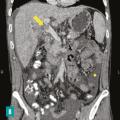

Les maladies vasculaires du foie sont des maladies rares et leur diagnostic peut parfois être difficile, tardif, conduisant à un retard de prise en charge délétère pour le malade. Il est le plus souvent multidisciplinaire, faisant intervenir au premier plan le clinicien mais également le radiologue et l’anatomopathologiste.

Le syndrome de Budd-Chiari (SBC) est une affection rare caractérisée par une obstruction du drainage veineux hépatique, commençant au niveau des veinules hépatiques jusqu’à la partie terminale de la veine cave inférieure. Il peut se manifester par un tableau d’hépatite fulminante, notamment en cas d’obstruction complète des trois…

Les atteintes possibles des petits vaisseaux du foie sont au nombre de quatre (fig. 1)  :la maladie vasculaire porto-sinusoïdale (MVPS)  ;le syndrome d’obstruction des sinusoïdes, appelé également «  maladie veino-occlusive  », caractérisé par l’obstruction des sinusoïdes et des veinules hépatiques par des…

La thrombose de la veine porte (TVP) se caractérise par l’obstruction, le plus souvent par un thrombus, de la veine porte et/ou de ses branches portales (droite et/ou gauche). Cette obstruction peut être partielle ou complète, récente (moins de six mois) ou chronique (plus de six mois) et peut également affecter les vaisseaux…